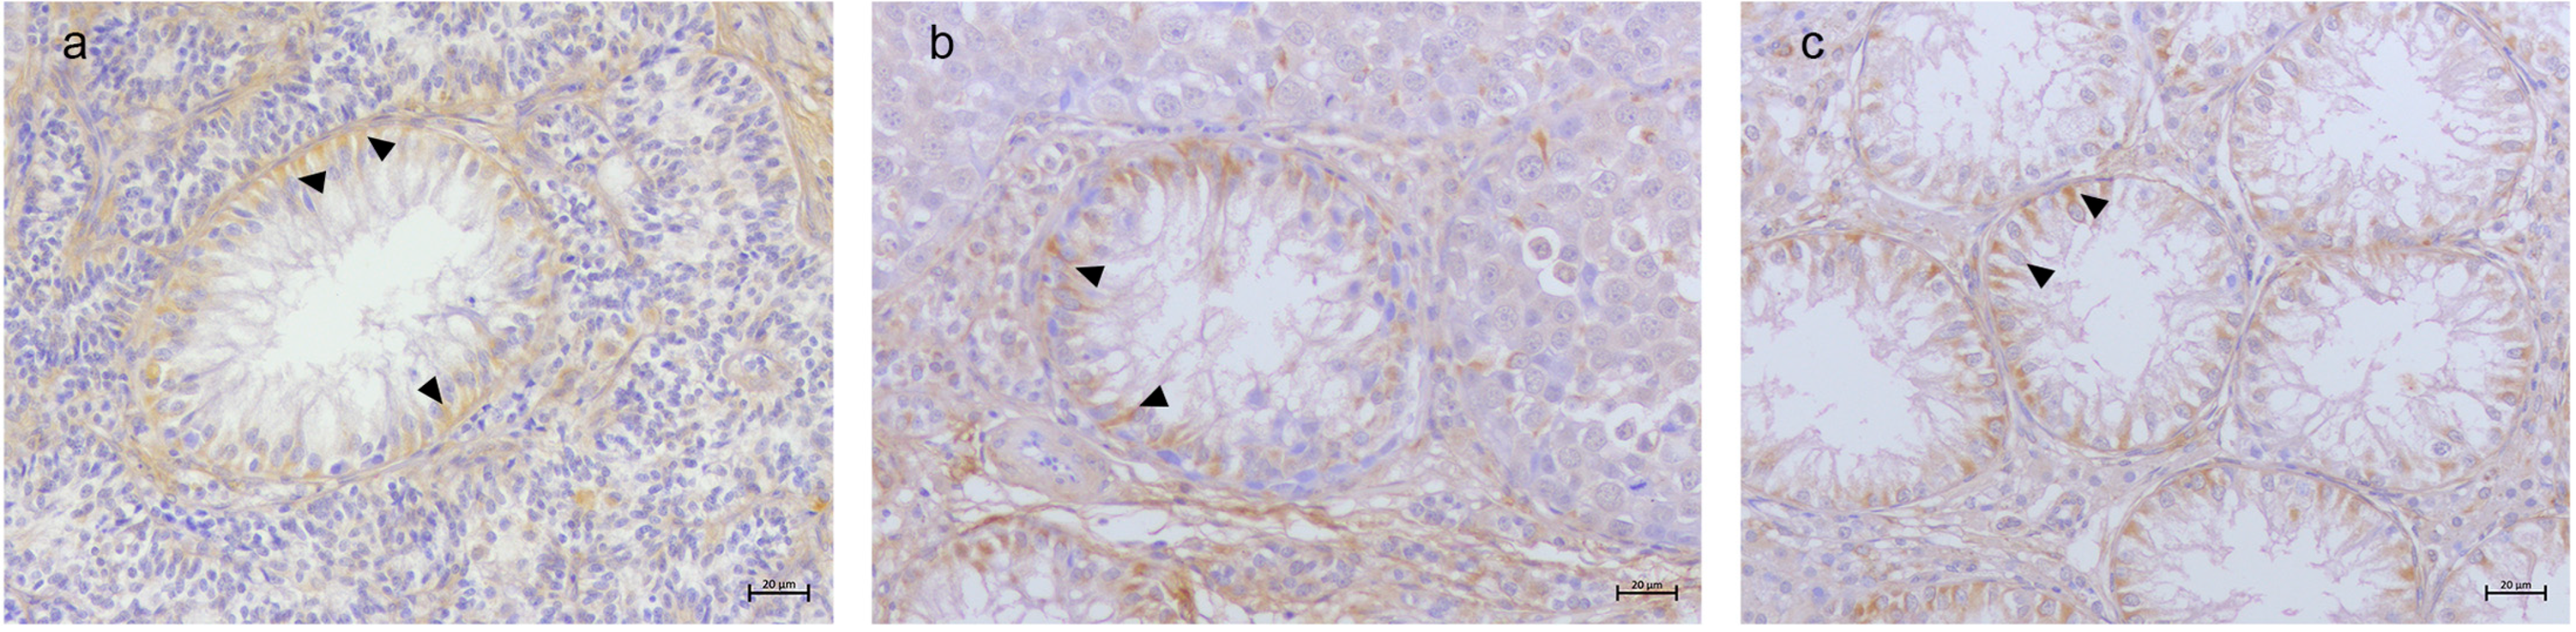

3.2. Immunohistochemical Results